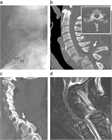

1. CT、MRI:MRIは脊椎と脊髄の同時評価が可能であり有用性が高い。しかし撮像時間を有するならCTを優先させる(推奨度1)